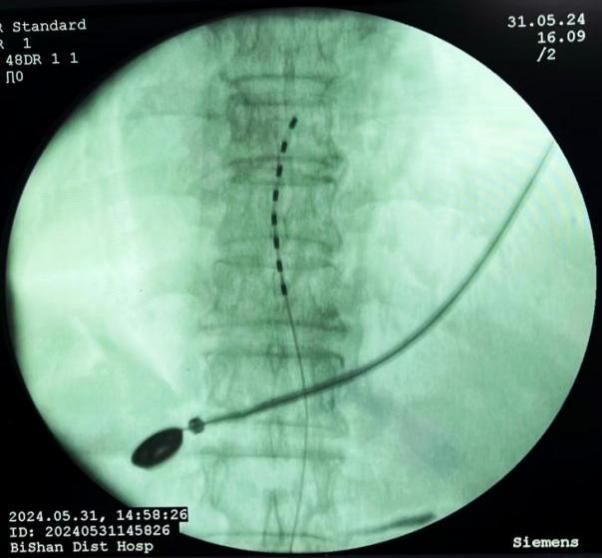

脊髓电刺激植入术:将电极植入脊柱附近硬膜外腔,通过电流刺激脊髓,阻断疼痛信号传至大脑,有效治疗慢性顽固性神经痛。

脊髓电刺激植入术